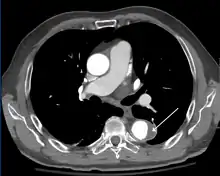

Follow-up

Closure of the lumen of a Type B aortic dissection following medical management

The long-term follow-up in individuals who survive aortic dissection involves strict blood pressure control. The relative risk of late rupture of an aortic aneurysm is 10 times higher in individuals who have uncontrolled hypertension, compared to individuals with a systolic pressure below 130 mmHg.

The risk of death is highest in the first two years after the acute event, and individuals should be followed closely during this time period. About 29% of late deaths following surgery are due to rupture of either a dissecting aneurysm or another aneurysm. In addition, a 17% to 25% incidence exists of new aneurysm formation, typically due to dilatation of the residual false lumen. These new aneurysms are more likely to rupture, due to their thinner walls.

Serial imaging of the aorta is suggested, with MRI being the preferred imaging technique.